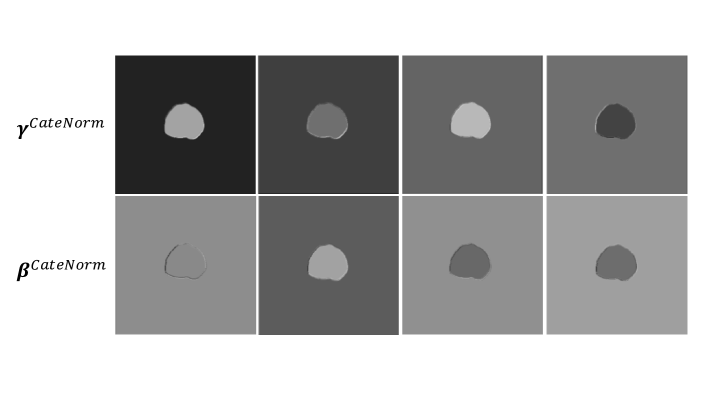

Visualizing activations in CateNorm: Appendix Figure 6 visualizes the learned γCateNormsuperscript𝛾CateNorm\gamma^{\textup{CateNorm}} and βCateNormsuperscript𝛽CateNorm\beta^{\textup{CateNorm}} on different channels of the intermediate CateNorm layers during the second forward. With prior class information as guidance, CateNorm can modulate spatially-adaptive parameters. Such spatial-wise modulation can be complementary to the channel-wise modulation accomplished by BN, and derives more discriminative features that benefit segmentation.

Figure 6: CateNorm does normalize with semantic information. This figure visualizes the learned γCateNormsuperscript𝛾CateNorm\gamma^{\textup{CateNorm}} (1st row) and βCateNormsuperscript𝛽CateNorm\beta^{\textup{CateNorm}} (2nd row) of a CateNorm layer in a CateNorm block on different channels of the intermediate CateNorm layer during the second forward. With prior class information as guidance, CateNorm can modulate spatially-adaptive parameters. Such spatial-wise modulation can be complementary to the channel-wise modulation accomplished by BN, and derives more discriminative features that benefit segmentation.